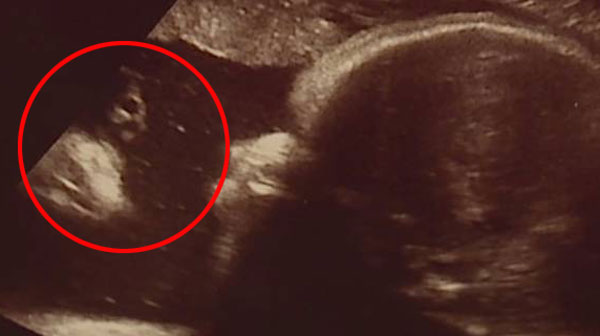

구순구개열 수술 전후의 차이

구순구개열 수술 방법 전후 차이 구순 구개열 수술 방법 전 후 구순구개열 수술 방법 차이 전 후 구개열: 왜인지 알고 싶으신가요? 자연스럽게 뜨거운 입을 뜨거운 입이라고 하고, 자연스럽게 뜨거운 입을 뜨거운 입이라고 합니다. 태어날 때부터 입술과 입천장은 완전히 다른 위치에 만들어졌지만 두 부분은 서로 매우 가깝습니다. 결과적으로, 구개열이 있는 어린이는 구개열이 있을 수 있고, 어린이는 구개열이 있을 수 있으므로 구개열이라는 이름이 붙습니다. 오늘은 자궁경부 확장술에 대한 정보를 공유해 드리고자 합니다. 자궁경부 탈출증의 원인으로는 유전적 질환, 개복술 시술, 임신 후 정확한 초음파 소견 등이 있습니다. 14주. 우리나라에서는 약 600~1000명 정도에서 발생합니다. 대개 임신 4~7주 사이에는 얼굴과 입천장을 구성하는 조직이 제대로 접착되지 않거나 접착되지 않아 눈에 문제가 발생할 수 있습니다. . 구강 및 구강질환의 원인은 다양한 요인들의 종합적인 작용에 의해 발생됩니다. 따라서 유전적인 원인만으로 설명하기는 어렵습니다. 구강 및 구강 질환의 원인: 유전적 요인이 많나요? 입을 벌리는 정확한 원인은 과학적으로 명확하지 않습니다. 그러나 유전적 요인과 환경적 요인이 상호작용에 의해 발생하는 것으로 알려져 있다. 부모나 형제자매 사이에 입이 찢어질 확률이 높아집니다. 환경적 요인은 약물과 담배로 인해 발생할 수 있습니다. 최근 유전적 사례는 극히 드뭅니다. 임산부가 임신 중 약을 복용하면 저산소증, 홍역 등으로 인해 엽산과 비타민C의 결핍이 장기간 지속됩니다. 청력징후 : 임신 14주 이후 질병 의심, 21주째 청력상실 임신주 : 구강초음파 임신 14주차에는 추후 확진이 가능하며 경추 초음파 검사도 가능합니다. 경추 질환 선천성 유전질환은 아기가 태어나기 전 임신 중 경추 초음파를 통해 진단됩니다. 보통 임신 14주쯤에 의심됩니다. 거의 정확한 진단에는 입이 열려 있는지 확인하기 위해 거의 3D 초음파로 얼굴을 검사하는 것이 포함됩니다. 정확한 기간은 없으나, 최소 14주, 특히 21주 이후에는 개구초음파를 실시해야 합니다. 초음파 진단 후 입술이 갈라질 정도로 지방이 일주일 정도 남아 있는 것으로 확인된다면 임신 중에는 주의가 필요하다. 특별한 주의사항은 없습니다. 3~5개월 정도 소요됩니다. 발달 정도에 따라 8~12개월 후에 1차 구순구개열 수술을 시행할 수 있습니다. 구순구개열 2차 수술은 학령기 이전에 시행하고, 성인 이후에는 증상 검사에 따라 구순구개열 수술 계획을 조정합니다. 입술과 입천장에서 떨어진 곳에 작은 입구가 여러 개 있고, 코의 모양도 변할 수 있으며, 자라면서 작은 입도 보일 수 있다. . 구순구개열 수술용. 3~5개월 이내가 됩니다. 그리고 구순구개열 수술과 달리 구개열을 치료하기 위한 구순구개열 수술은 정상 연령에서도 시행이 가능합니다. 어릴 때 구순구개열 수술을 한 것보다 8~12개월 늦어서 입술이 조여지기 때문에 출산 후에도 관리가 필요합니다. 젖꼭지나 손가락을 빨면 봉합이나 흉터가 더 심해질 수 있습니다. 또한, 코 모양을 유지하기 위해서는 코몰드를 6개월 정도 붙이고, 테이프를 3개월 정도 붙여서 흉터가 크고 두꺼워지지 않도록 해야 합니다. 구순구개열 조기 수술이 중요한 이유 구강 및 구강 질환을 진단한 후, 아이가 성장하면서 2차적인 문제가 나타나 구순구개열, 코, 흉터 등의 문제가 발생할 수도 있습니다. 따라서 취학 연령 이전에 추가 치료가 필요할 수 있습니다. 남자는 18세까지, 여자는 16세까지 성장하기 때문이다. 심한 구순구개열은 청력손실을 예방하기 위해 정상적인 폐색을 방해할 수 있으나, 정상적으로 교정되지 않을 경우 구순구개열 수술이 필요할 수 있습니다. 구순구개열 수술은 대개 대학 입학 전과 입시 이후에 입천장을 분리한 후 시행하는 것이 일반적이다. 점액만 분리할 수 있습니다. 이런 경우에는 구순구개열 수술이 필요하지 않을 수도 있습니다. 그러나 점막은 뚜렷하고, 막성, 막성, 막성, 막성, 막성, 막성, 막성, 막성입니다. 언어평가 결과 언어장애가 발견되면 구순구개열 수술을 2~3회 시행할 수 있습니다. 3 년. 구순구개열 수술 후 한달 정도는 죽과 국을 드셔야 합니다. 구순구개열 수술 후 상처가 낫는 데는 약 한 달 정도 걸립니다. 그러므로 한 달 동안은 상처를 자극하지 않도록 해야 합니다. 실밥은 구순구개열 수술 후 5~7일 이내에 제거할 수 있으나 완전히 닫히지 않도록 주의하시기 바랍니다. 상처가 재발할 수 있으므로 한 달에 한 번 정도는 주의하세요. 구순구개열 수술 후 수술 흉터도 관리해야 합니다. 구순구개열 수술 후 3주간은 딱딱한 음식이나 밥을 피하고, 회복을 위해 순한 음식을 섭취하며, 1개월간은 빨대나 칫솔 등 이물질을 입에 넣지 않도록 주의하세요. 클라우드블루 : 구강초음파 이후에는 부모님의 마음이 가장 중요합니다. 장루의 정확한 원인은 알려져 있지 않으므로 예방법은 없습니다. 그러나 엽산과 함께 비타민이 함유된 산모 보조제를 함께 복용하면 구강 발열 가능성을 줄일 수 있으므로 예방을 위해 이러한 보조제를 복용하는 것이 좋습니다. 구제역 진단을 받은 부모들은 자녀가 건강하게 자랄 수 있도록 열린 마음을 가져야 합니다. 구순구개열 수술은 개인의 얼굴 성장과 형태, 특성에 영향을 미치기 때문에 적절한 시기와 절차에 따라 분류하여 수술을 받는 것이 중요합니다. 일반적으로 수술은 출산 후 3개월 이후부터 가능하며, 청소년의 경우 심한 코 합병증이나 비뚤어진 입술과 함께 구순구개열 수술을 시행합니다. 성인이 되어도 증상이 호전되지 않으면 구순구개열 수술을 시행합니다. 골격적인 문제와 부정합적인 문제를 동시에 치료합니다. 이러한 절단은 모든 성장과 발달 후에 이루어져야 하며 주의 깊은 연구가 필요합니다. 장기간 치료가 필요한 질병이 있습니다. 그리고 간호직원과 환자 3명의 협조가 필요합니다. 선천적인 원인으로 오해하기 쉽지만 지속적인 구강관리와 수술로 치료합니다. 환자는 정상적인 사회 활동에 참여할 수 있습니다. 그러므로 가장 중요한 것은 마음을 안정시키는 것입니다. 완벽한 결과를 얻기 위해서는 정확한 진단을 통해 환자 개개인에게 꼭 맞는 맞춤형 치료를 받는 것이 필요합니다. 또한 모든 2차 질환을 치료할 수 있어 성형 전 어린이의 구강 초음파 검사에서는 거의 눈에 띄지 않습니다. 필수의. . 만들다. 하지만 속도의 차이와 조직의 성장 가능성으로 인해 코 연골의 변화, 입술 흉터 등의 2차 증상이 나타나게 됩니다. 이 경우 단일 측정, 양측 측정, 목 흉터 등 증상에 따라 치료 방법이 다르기 때문에 정확한 진단이 필요합니다. 점막입니다. 또한, 이러한 증상을 적시에 발견하고 치료하는 것이 매우 중요하므로, 부모는 아이의 구강 발달을 지속적으로 관찰하고, 비정상적인 증상이 나타나면 가능한 한 빨리 의사나 치과에 가서 상담과 진단을 받아야 한다. 영유아의 구강발달은 사람마다 다르기 때문에 일반적인 기준보다는 개개인의 성장속도를 기준으로 평가하는 것이 더 정확합니다. 구강 외에도 어린 아이들의 입과 입의 지속적인 발달을 모니터링하는 것이 중요합니다. 그렇지 않으면 언어 및 기타 발달 문제가 발생할 수 있으므로 부모는 자녀의 발달을 지속적으로 모니터링하고 필요한 경우 자녀의 건강 개선을 위해 전문가의 도움을 받아야 합니다.